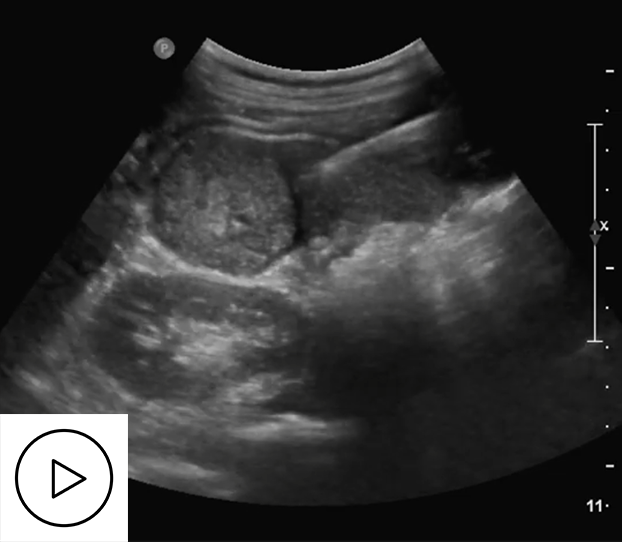

In conventional US-guided ablation (Figure 4), the physician typically places a few landmarks on in-plane 2D US images to estimate the required ablation zone. Although a 5–10 mm safety margin is commonly applied in clinical practice to reduce the risk of residual tumours, this approach may still fail to ensure complete tumour coverage. Moreover, to maintain procedural safety, the physician must carefully review multiple US views to avoid ablating critical structures such as the colon (Figure 5).

Assessment 1

Figure 4. Tumour coverage assessment on 2D US.